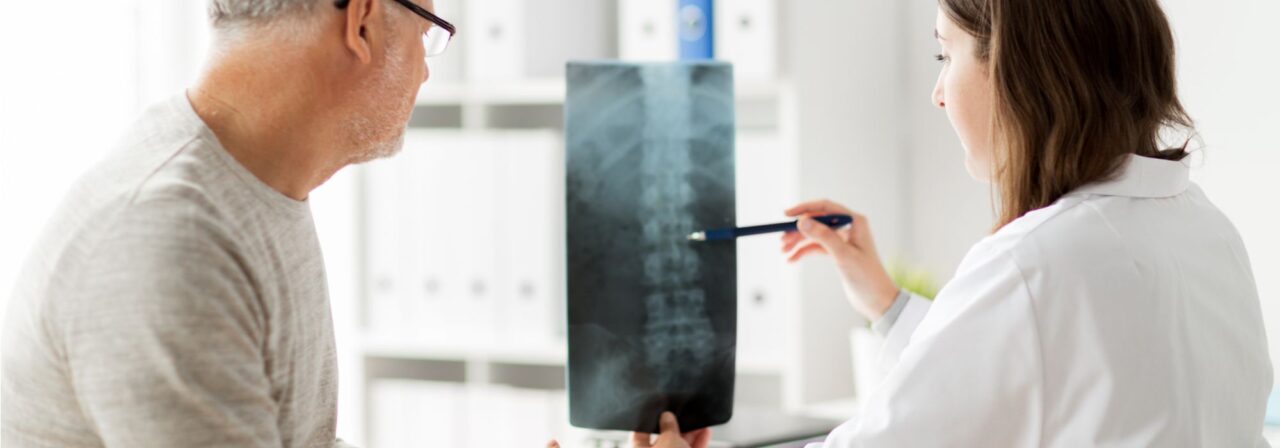

The Rothman Orthopaedics Spine Team annually performs more than 3,000 spine surgeries in the Philadelphia greater metropolitan area.

The Rothman Orthopaedic Institute’s spine team is known nationwide for its innovative and exemplary spinal treatments. Our specialists perform thousands of spine surgeries each year in the greater Philadelphia metropolitan area alone. These helpful spinal procedures treat problems resulting from degeneration of the cervical and lumbar discs, herniated discs, spinal stenosis, spinal deformity, tumors, trauma, and instability.

Our nationally recognized orthopedic team has consistently ranked among the best in the Delaware Valley by US News & World Report.